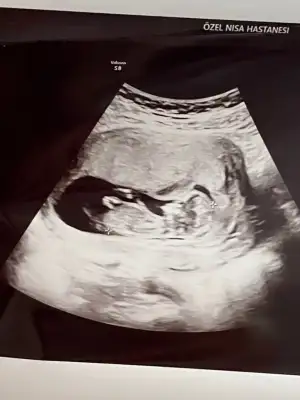

dr soylemeden siz gorun genital nub teorisi ( bebegin cinsiyeti)

Bana da tahmin yurutun ya lutefn 13 haftalık olduk teşekürler şimdiden

Bir de bu açıdan var sanki burda nubu daha belli Ikra meyra Ikra meyra ne dersin burda da erkek mi diyorsun?